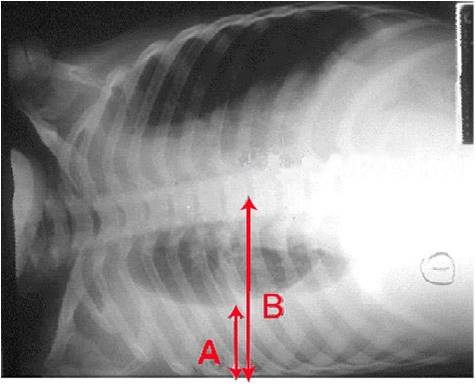

weekly clinical round for undergraduate from 8 to 11 AM during which interpretation of CHEST X rays was done for all cases of cardiothoracic surgery, gived by 2 staf member for 3 months